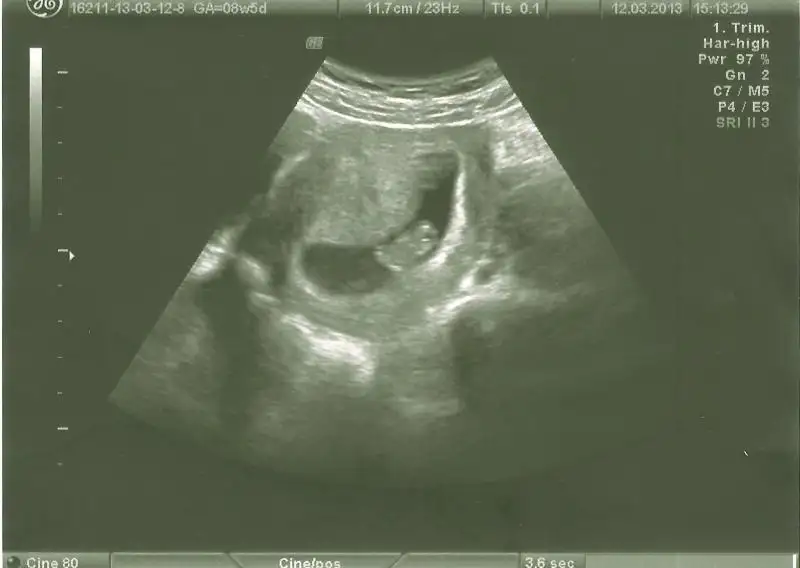

dr soylemeden siz gorun genital nub teorisi ( bebegin cinsiyeti)

bnde yorum bkliyorum kızlarr 2ncisi 11hafta bitiminde 2li tst günüydüü lütfeen

canim bu haftalarda paralel olup erkek cikan cok olduu simdilik paralel seninki 12 13 haftada bu skeil olsaydi kesin kiz derdim ama 11 haftada yorum yapamiyorum

evet bana da paralel geldi.dr da o hafta kıza benziyo dedi .ben 3.kıza hazırlıyorum psikolojimi.bir ihtimal belki rahat bir gebelik olması ve erkek belirtileri vermesi belki erkektir dedirtiyo ama nub ortada.

teoriye göre bakınca paralelse kız dikse erkek diyoruz ama ben bacaktan hiç ayırd edemiyorum bu nubu yahu...

canım daha erken ama benimkine de bir bakın :1:

haftaya yenilerini koyacağım